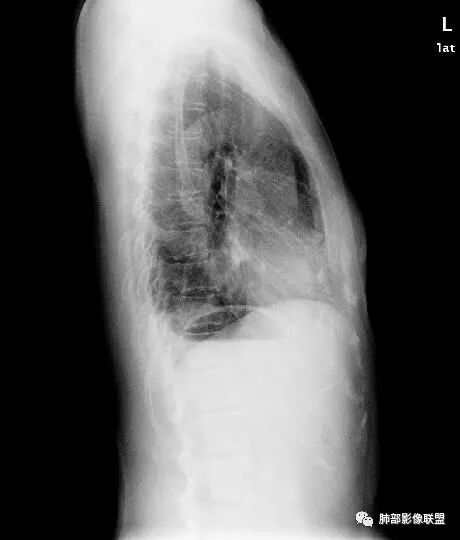

Shelia:侧位心后间隙变小,下肺野与心影重叠区怀疑有斑片影

正位实在看不出什么问题

Coke with ice:唉……我都没找出来病变在哪……平片的老师们指点指点南边:

Shelia:

南大标记的,我怀疑了,但是正位不知道在哪里远方:接第二部分:

看完第二部分大家再说说看有什么体会?宇宙星空:左侧膈面上片状高密度影

Coke with ice:平片真不容易观察。这里最常见的是什么毛病呢……后肋膈角,呃……疝?形态不太像疝。还有啥疾病谱,盘状肺不张?胸膜来源?

形态不太像疝。还有啥疾病谱,盘状肺不张?胸膜来源?

形态也不像肺不张的样子

M-Imaging :盘状不张不是,盘状不张,胖人腹压高多见远方:如南大所标示,标准答案。正位提示左肺下野与膈面重叠密度增高影,边缘光滑,侧位可再定位具体一点后肋膈角区密度增高影,具体是肺内肺外都有可能,盘状肺不张、肺内肿块、肺外病变(胸膜来源和膈肌来源)等都可以。我的体会常规正片再加负片结合这个肯定不会漏的,负片很有价值,平片发现问题就好,具体我们还是进一步CT检查了。